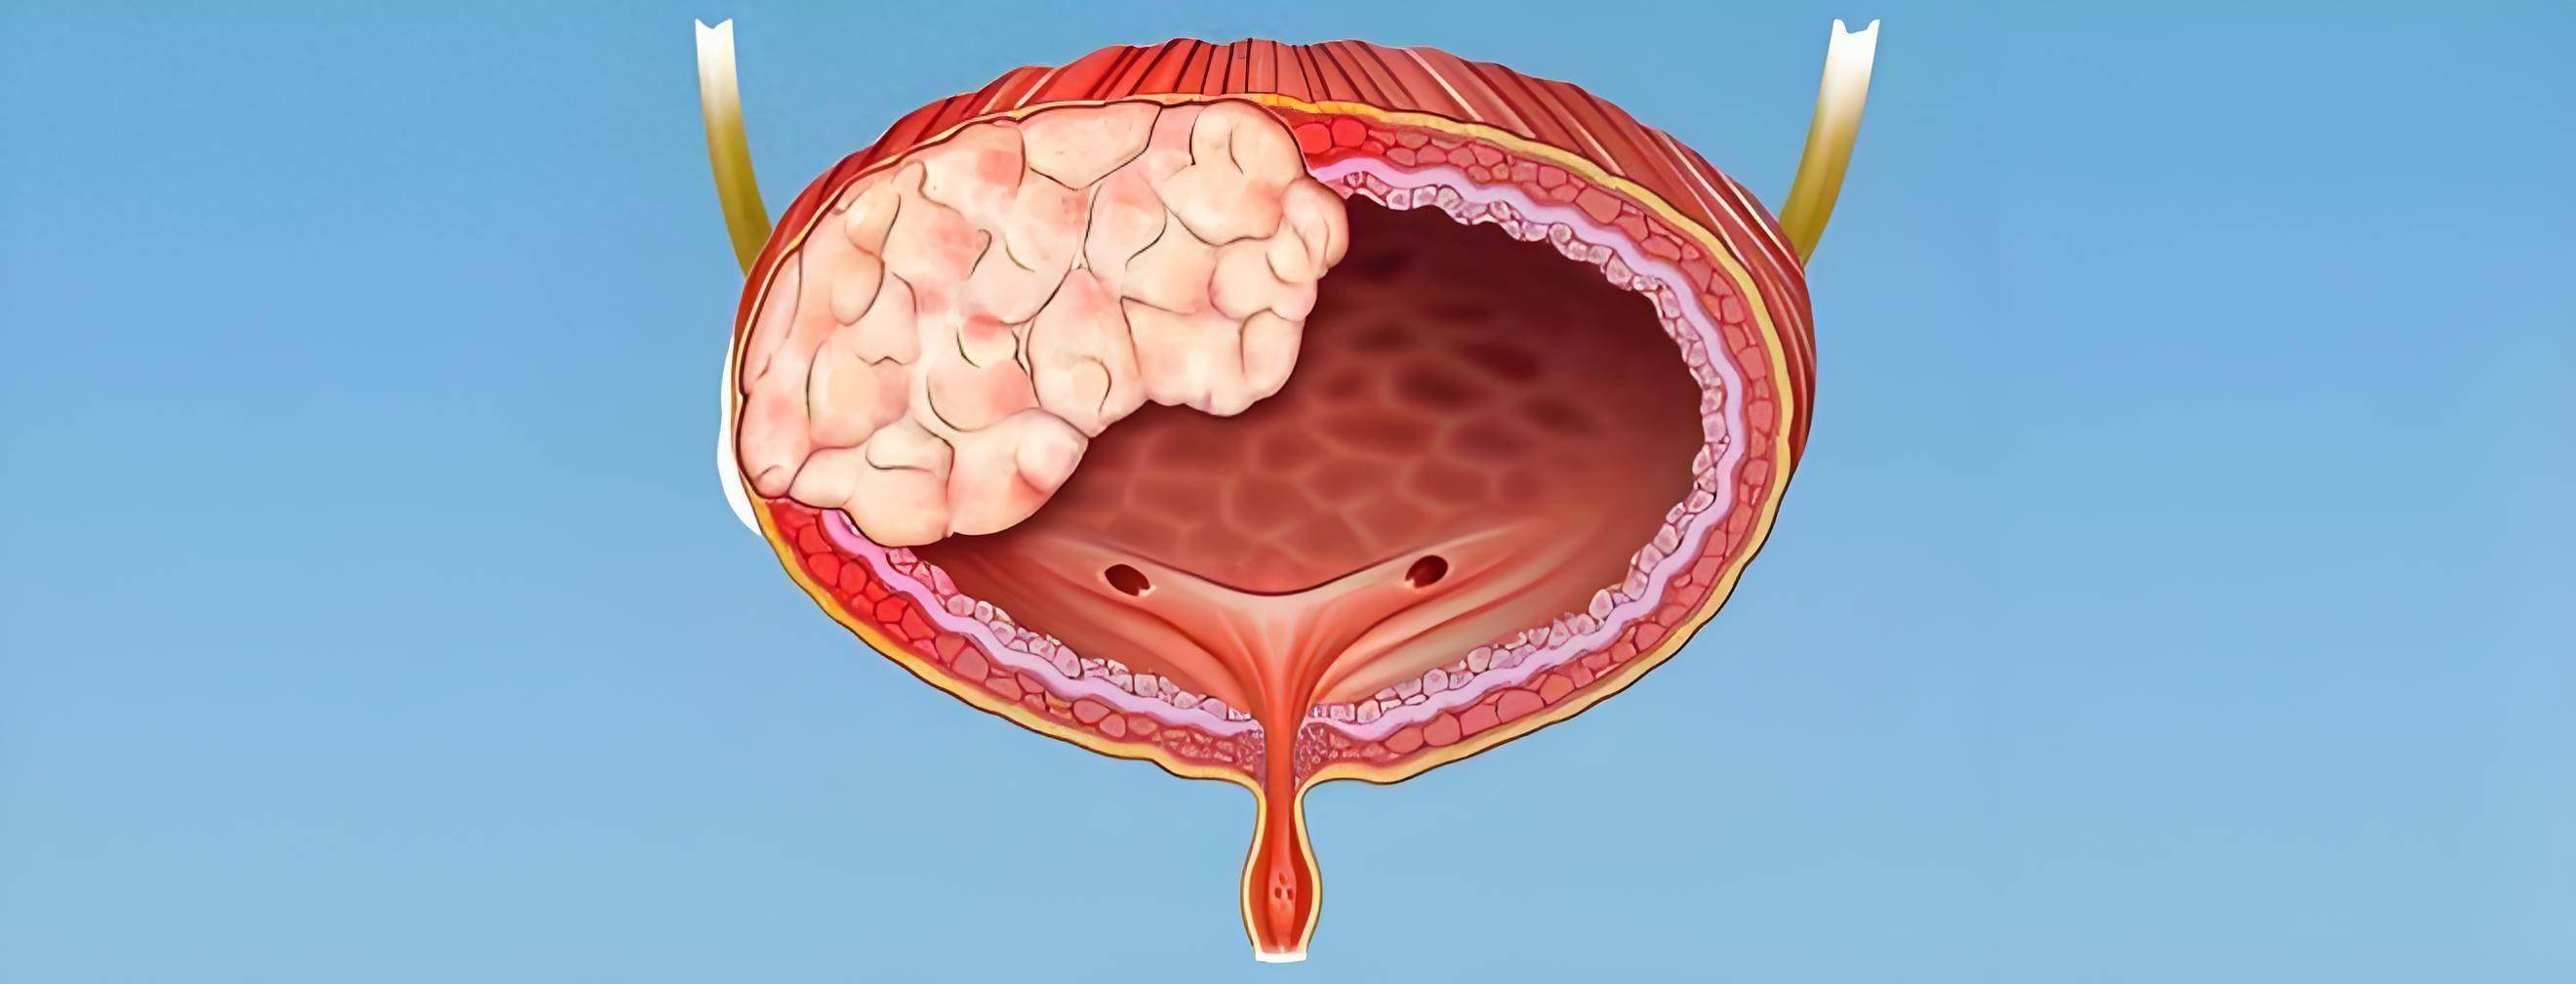

膀胱肿瘤的症状患者中约有75%一78%患有血尿,多呈无痛性或间歇性,血尿多是由于肿瘤破溃出血所致,血尿可多可少,多时肉眼便可看出,少时只是在显微镜下才能看到尿中有红细胞,膀胱癌的血尿一般为全程肉眼血尿,即整...【全文】

膀胱肿瘤属于泌尿系肿瘤中比较高发的,发病原因尚不能明确,但有调查显示长期吸烟和职业接触芳香胺的人比较容易患上膀胱肿瘤,此病的最佳治疗时间是早期的时候,所以了解膀胱肿瘤的症状很重要,那么膀胱肿瘤症状有哪...【全文】

膀胱癌是常见的恶性肿瘤,指膀胱原发的癌肿。依其浸润深度的不同,可分为原位癌或浸润癌,膀胱癌在泌尿系统各癌肿中,发病率较高。以间隙性无痛性肉眼血尿为特点,可伴尿频、尿急、尿痛等类似膀胱刺激症状,晚期有严...【全文】